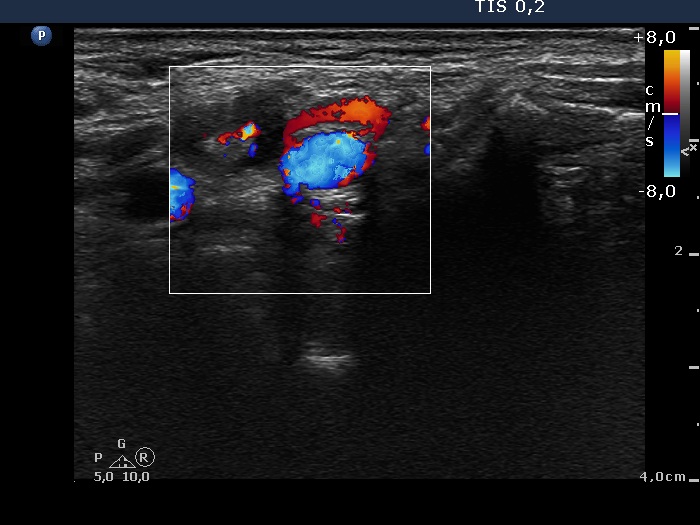

Ultrasonography: there were no thyroid parenchyma in the thyroid beds. A hypoechogenic mass was found lateral to the right lobe. This node presented an irregular hyperechogenic figure.

Because of the sonographic presentation we performed thyroglobulin determination from the wash out of the needle which resulted in 38 ng/mL. Serum-thyroglobulin was 3.4 ng/mL.